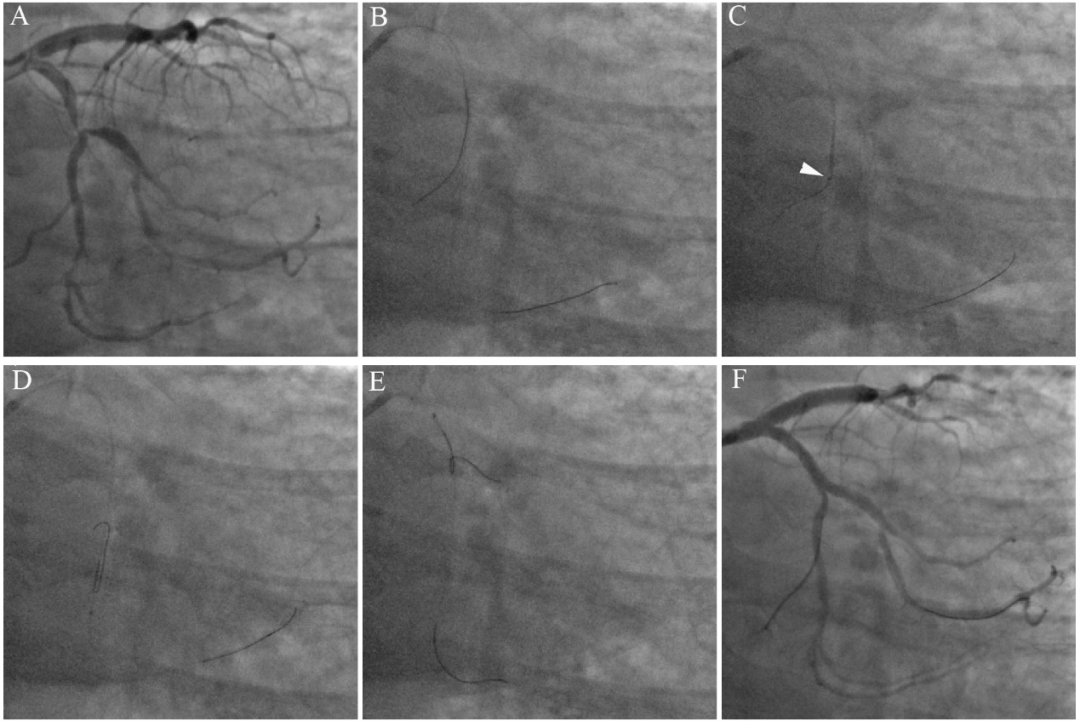

图4 体内反转导丝技术辅助回旋支分叉病变PCI。62岁男性,劳力性心绞痛。右桡动脉径路造影示回旋支中段严重狭窄,累及极度成角的钝缘支开口(A)。6 F EBU3.5指引导管到位,Runthrough导丝进入回旋支主支,Sion导丝反复尝试难以进入钝缘支,包括双腔微导管辅助下正向导丝操控技术均未能成功。最后采用体内反转导丝技术:经双腔微导管的OTW腔送入反转导丝(SION black,未塑反折弯,前端4mm正常塑形),送入靶分叉钝缘支以远的心房支约25mm(B)。将双腔微导管中心腔出口送至心房支开口处(C),将“反转导丝+双腔微导管”作为一个整体同时前送,SION black体内形成反转袢(D),直至反转导丝脱离心房支。其后操作同经典反转法:逐渐回撤“反转导丝+双腔微导管”,并微调反转导丝方向进入靶钝缘支(E)。最终回旋支-钝缘支置入支架并最终球囊对吻,结果良好(F)。